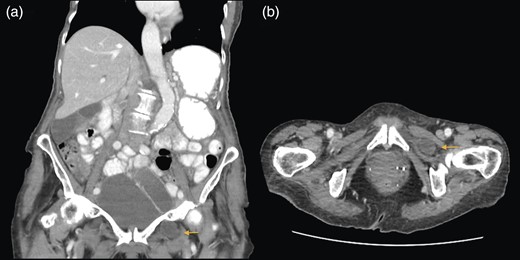

A 88-year-old woman presented to the ED with abdominal pain, vomiting, right hip pain and diarrhoea. Medical co-morbidities include ischaemic heart disease, hypertension and bilateral osteoarthritis of the hip. Her surgical history includes three Caesarean sections, open cholecystectomy, umbilical hernia repair and left mastectomy for breast cancer. A computed tomography (CT) abdomen revealed small bowel obstruction due to the right OH (Fig. 1) and evidence of a small left OH. A trial of conservative management was made for patient due to her age, multiple co-morbidities and patient's wishes. Bowel obstruction resolved with conservative management. The patient re-presented 1 month later with small bowel obstruction and pain radiating down medial left leg. There were no clinical signs of intestinal ischaemia. Abdominal x-ray was consistent with small bowel obstruction (Fig. 2) and CT abdomen revealed transition point at left OH (Fig. 3). A decision was made to proceed with midline laparotomy and bilateral OH repair. Intra-operatively, there was a large right OH containing a small bowel, which was reduced, and a bard polypropylene mesh plug inserted into the defect and fixed with prolene interrupted sutures. The left OH was smaller and was repaired primarily with prolene. The patient made an unremarkable recovery, and she was discharged 3 days after the operation. No recurrence was noted within a year of follow-up.

(a and b) Small bowel obstruction secondary to a left OH. (a) Coronal and (b) axial.